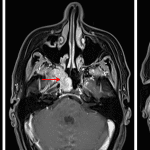

Age: 57

Sex: Female

Indication: Chronic sinusitis

- Enhancing right eccentric skull base mass measuring up to 3 cm involving the right sphenoid sinus, pterygopalatine fossa, vidian canal, and sphenopalatine foramen with enhancing soft tissue abutting the right carotid canal

- T1 signal hypointensity and enhancement in the right pterygoid process

- Enhancing mass in the left nasal cavity along the inferior turbinate measuring up to 1.7 cm

- Enhancing mass centered near the left piriform aperture measuring up to 1.7 cm

- Enhancing mass in the right nasolacrimal duct measuring up to 3.3 cm with associated dilation of the lacrimal sac

Rosai-Dorfman disease